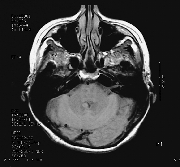

MRI showed a soft tissue lesion in the fourth ventricle (Fig. 1). This was consistent with a probable subependymoma which was thought to be an incidental finding. There was evidence of frontal lobe atrophy (Fig. 2).

figure 1

Figure 1. MRI T-2 study showing a fourth ventricle lesion likely an ependymoma.